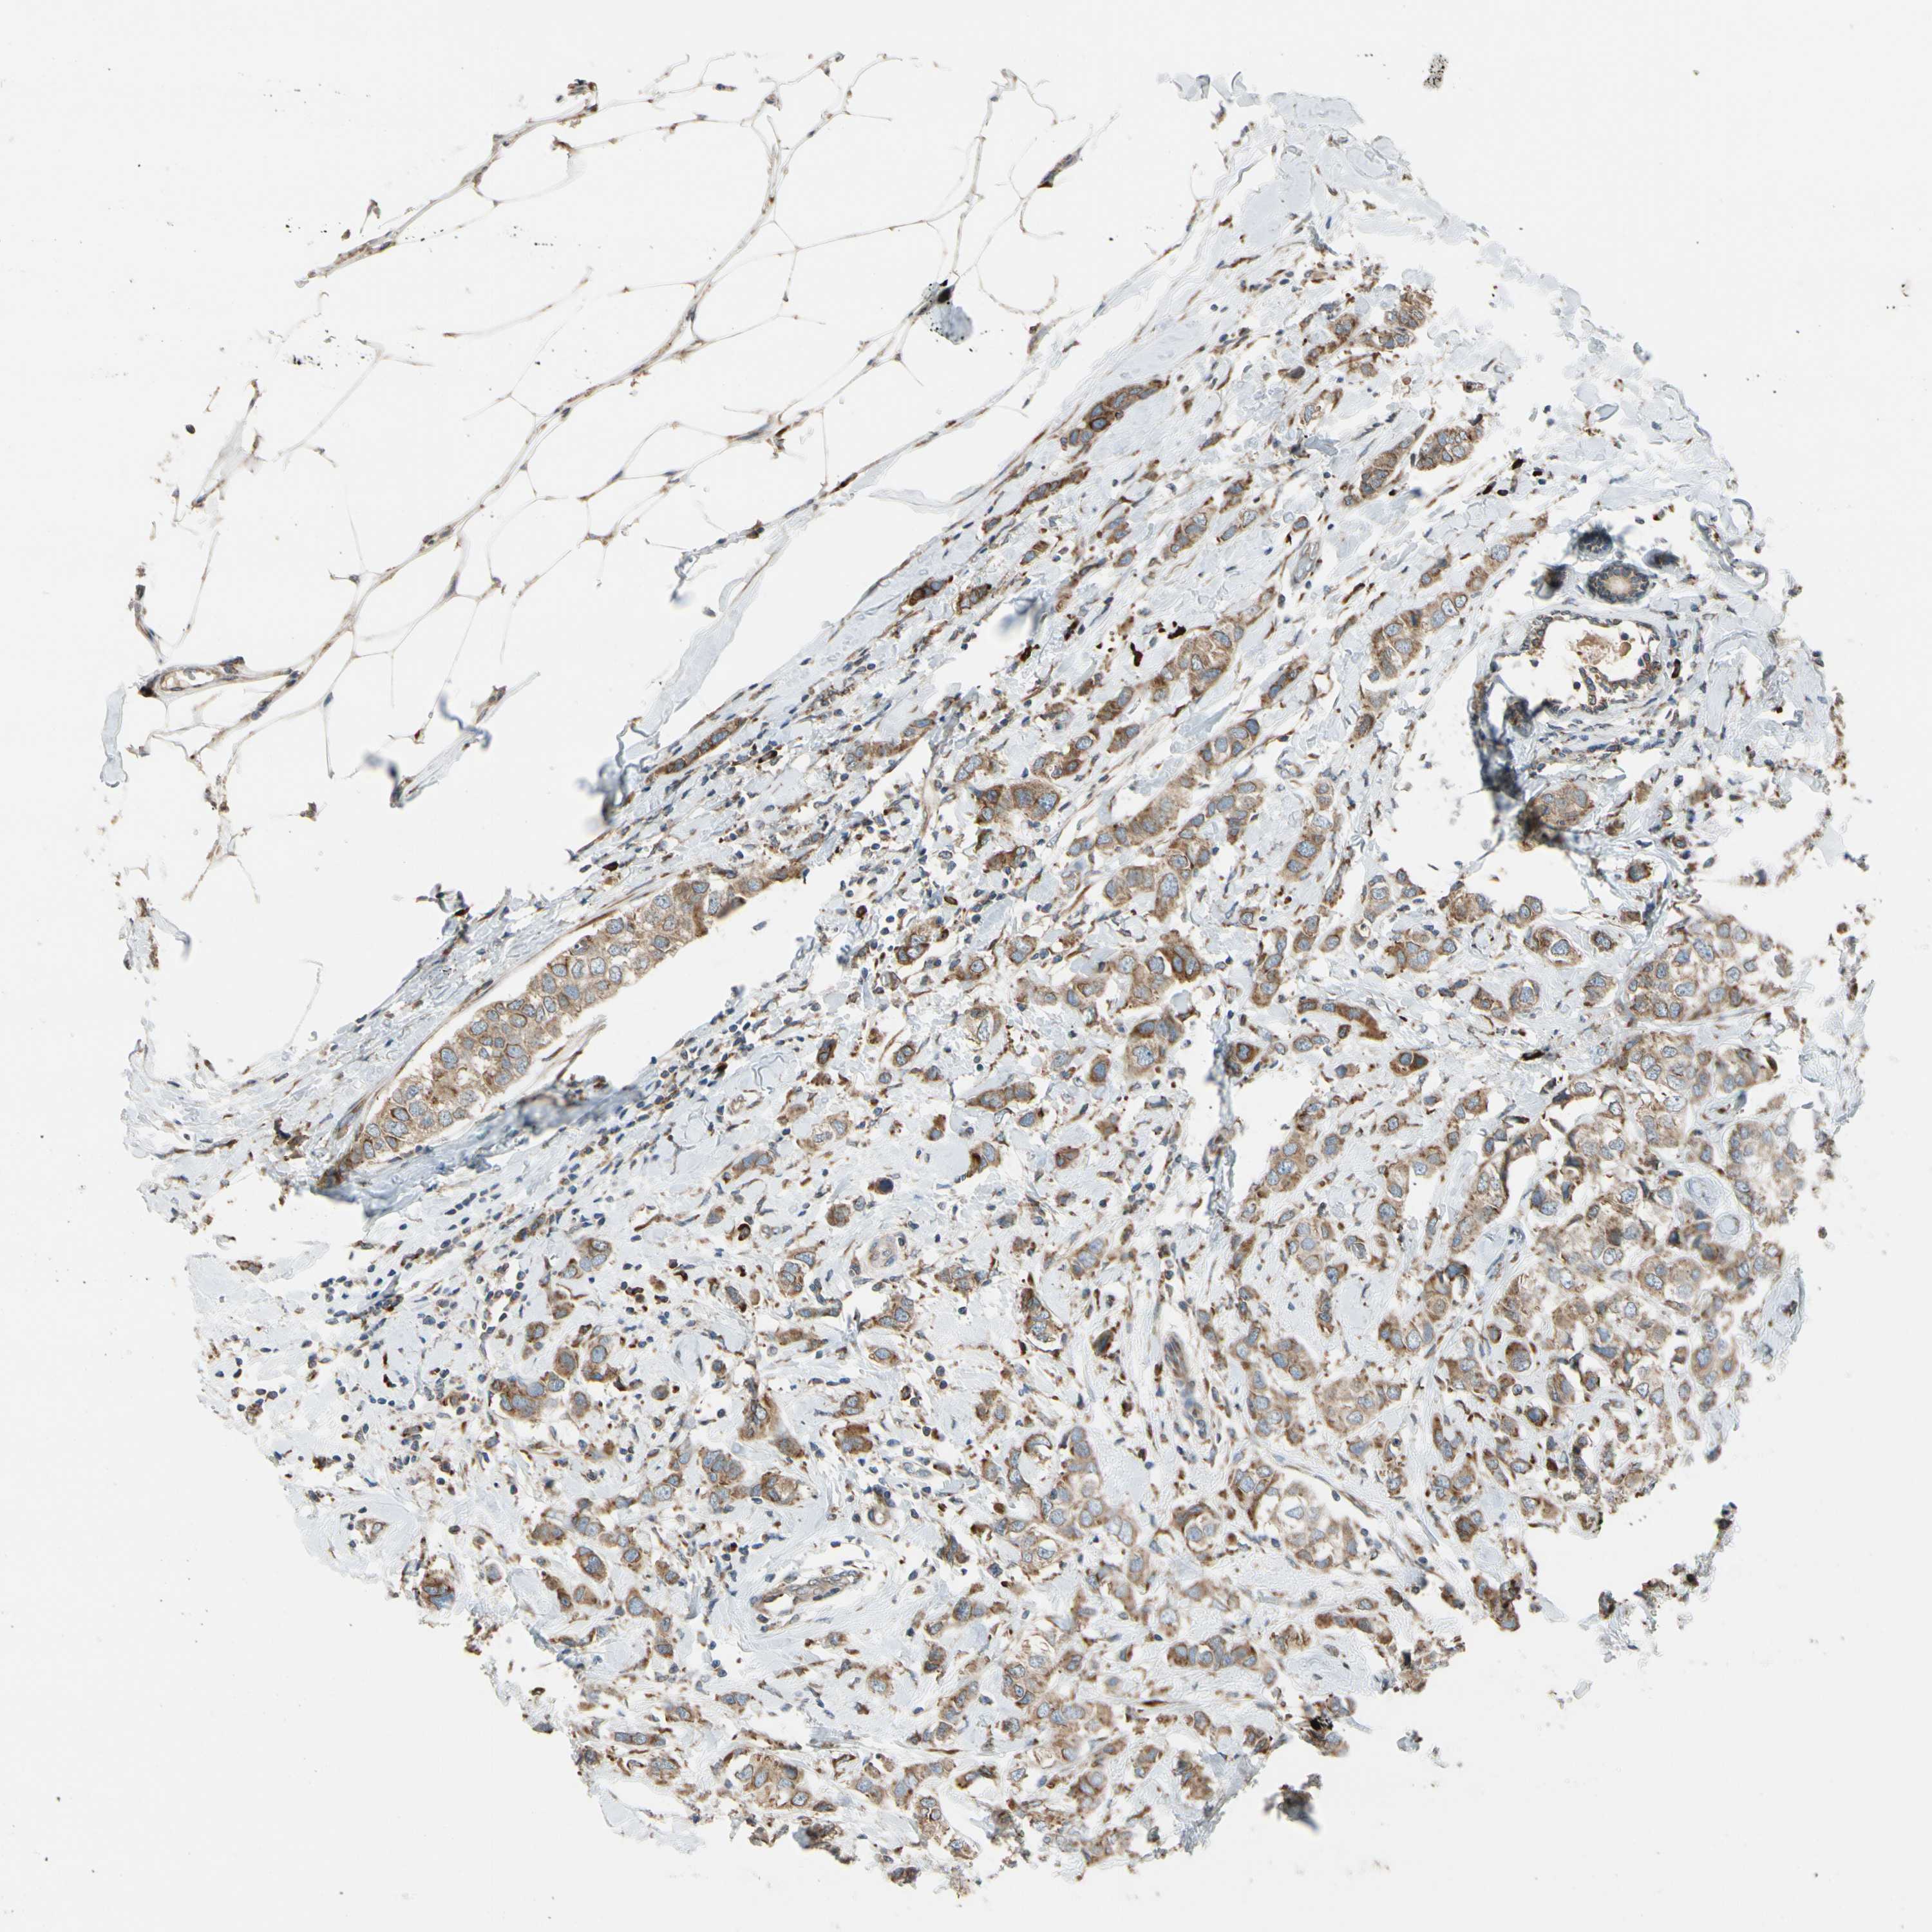

CANCER BREAST CANCER Show tissue menu

BRCA TCGA BRCA VALIDATION PROTEIN EXPRESSION

Breast cancer

Human cancer